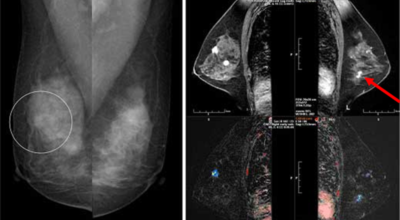

유방암 초기증상 - 유방의 혹

보통 응어리가 잡히는 분들의 40%는 물혹으로 가벼운 질병으로 바로 치유가 되는 경우가 많은데요 20~30%의 확률로 유방암일 가능성이 있다고 합니다. 따라서 매일같이 자신의 가슴을 마사지 해주시다 어느날 응어리가 잡히게 된다면 유방암 검사 초기에 받아 보시기를 권해 드려요.